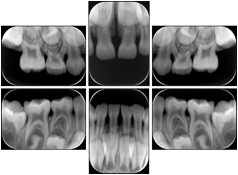

OO.1.3 Cardiology

Cardiac stress testing acquires images in at least two patient states, rest and stress, and typically with several different views of the heart to highlight function of different cardiac anatomic regions. Image review typically involves simultaneous display of the same anatomy at two patient states, or multiple anatomic views at one patient state, or even simultaneous display of multiple anatomic views at multiple states. This applies to all cardiac imaging modalities, including ultrasound, nuclear, and MR. The American College of Cardiology and American Society of Nuclear Medicine have adopted standard display layouts for nuclear cardiology rest-stress studies.

Stress Echocardiography Structured Display

Figure OO-5. Stress Echocardiography Structured Display

Stress-Rest Nuclear Cardiography Structured Display

Figure OO-6. Stress-Rest Nuclear Cardiography Structured Display